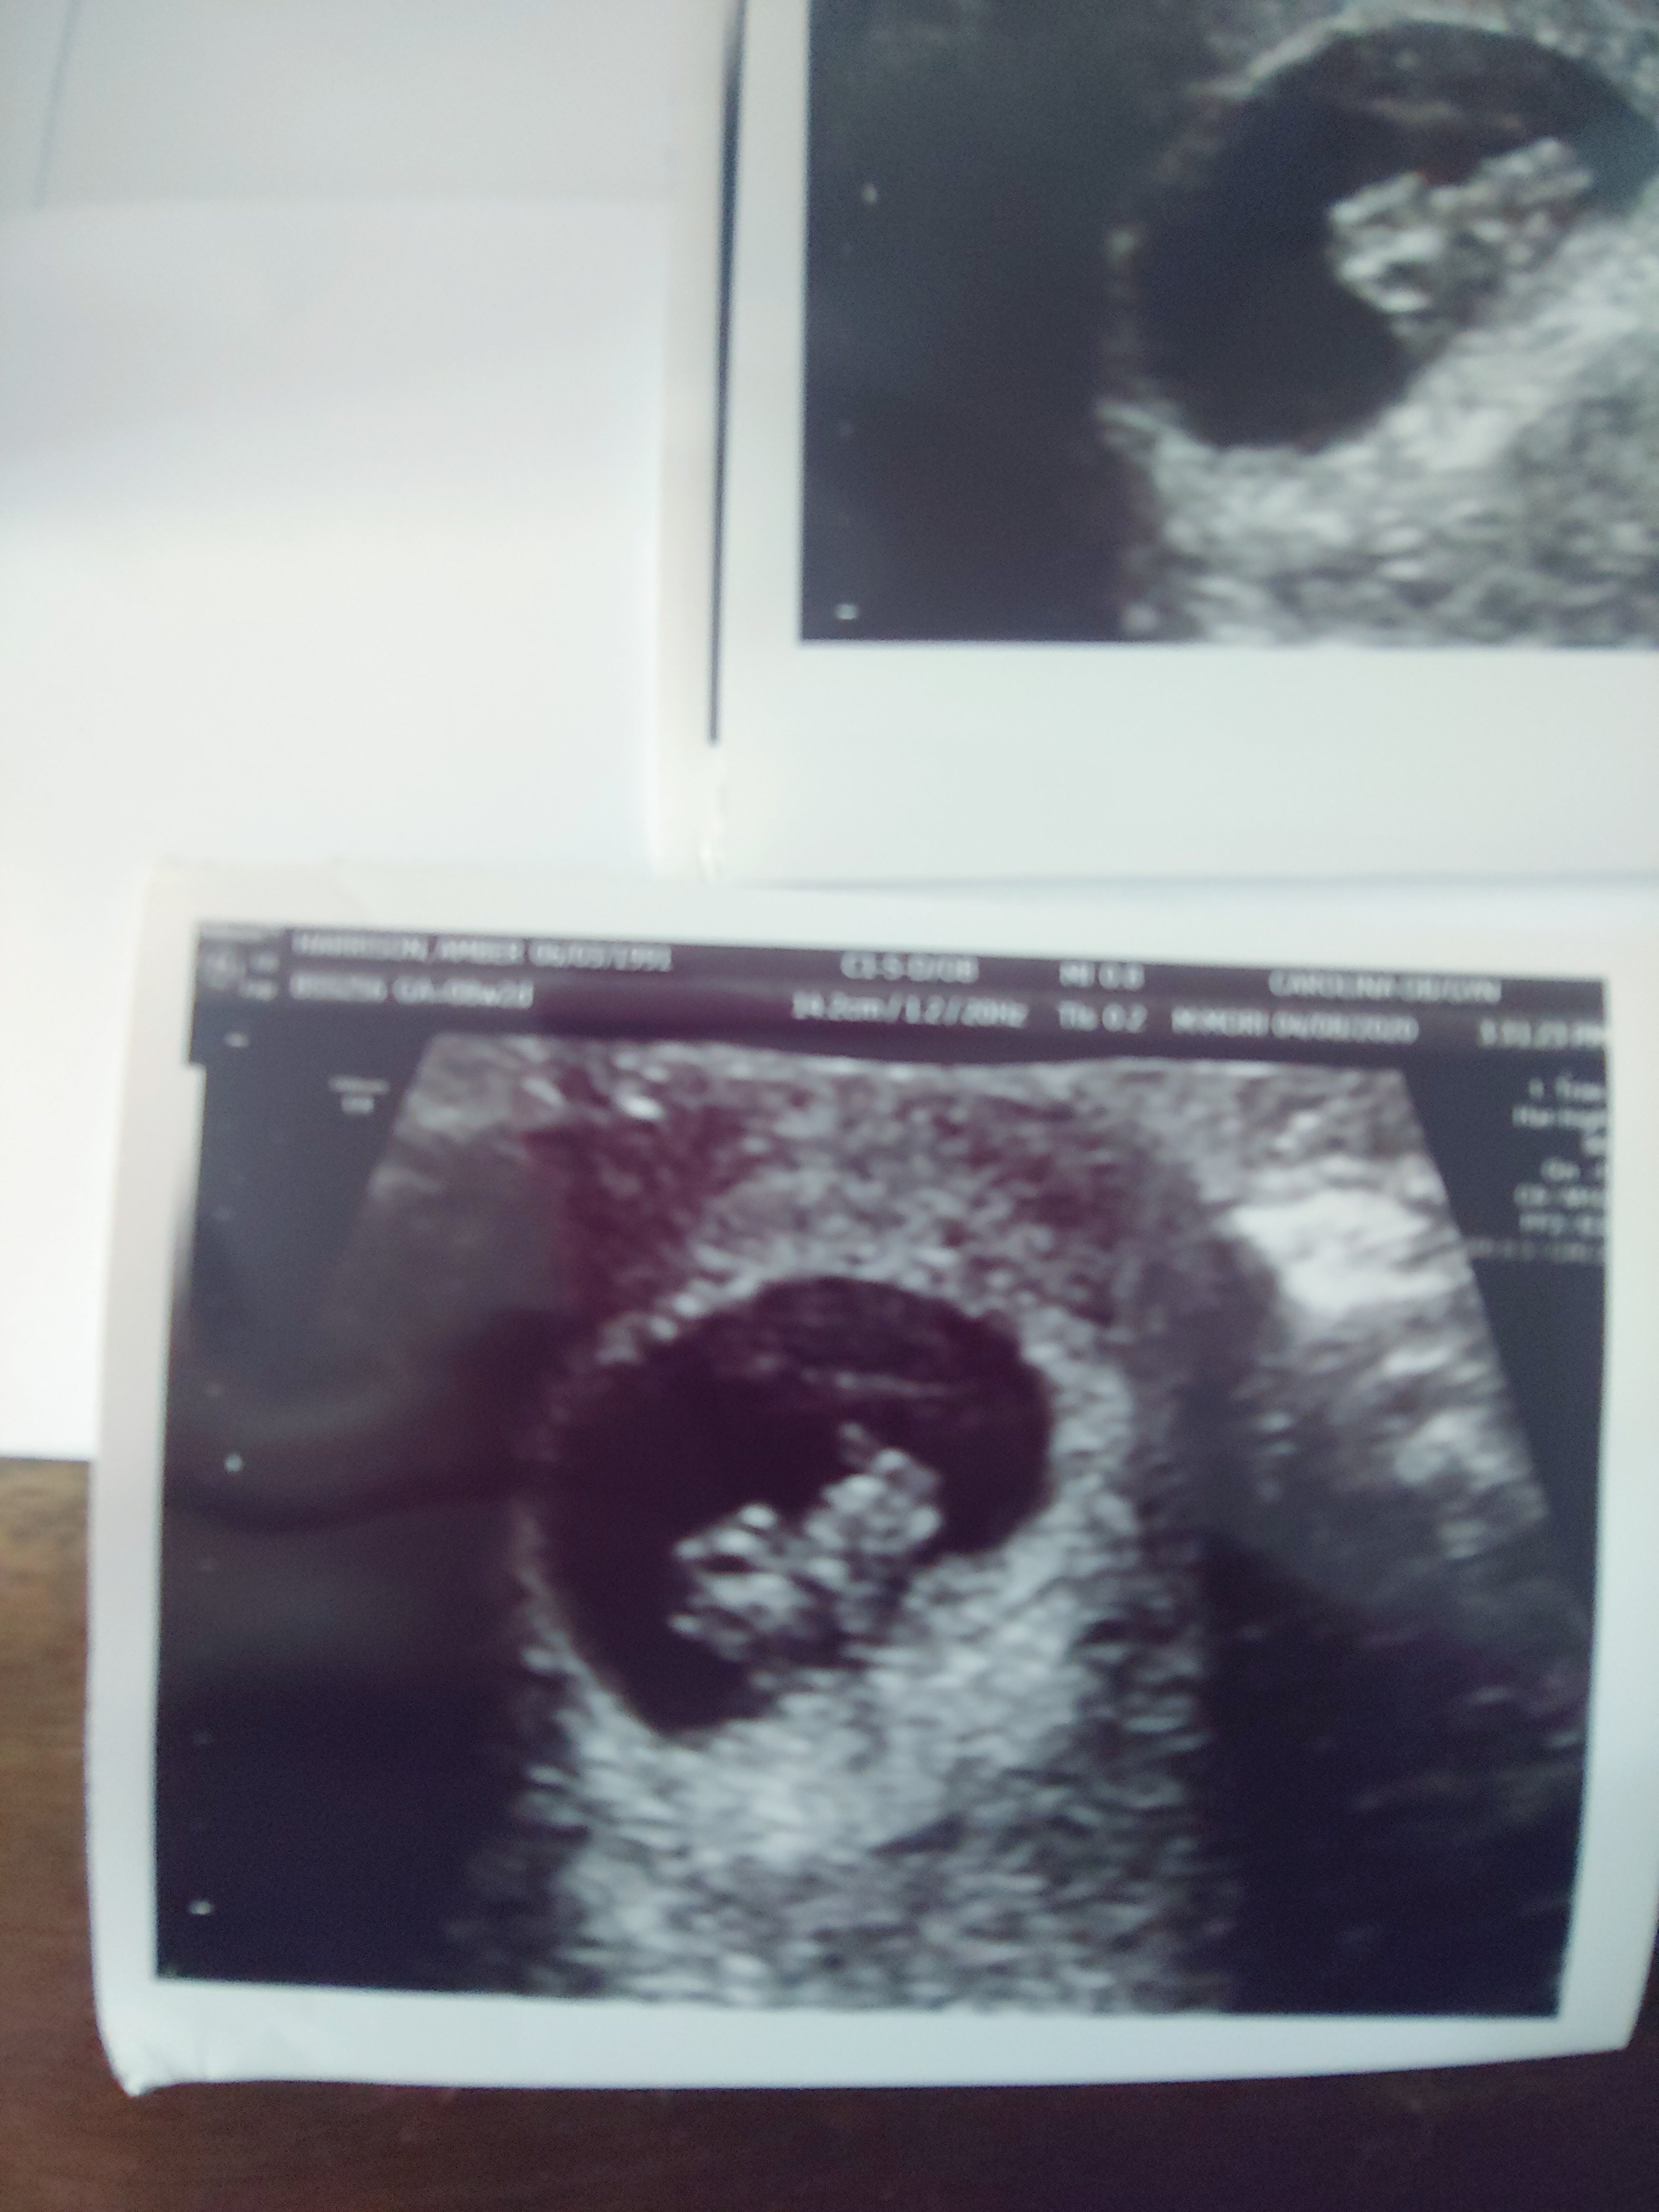

My wife and I were wanting to have a child but not spend thousands on thousands of dollars doing so. I did research, and there are a few products like Mosie on the market, but Mosie had the best reviews and so many stories. So we found a local donor that was able to give a fresh sample. We had him health tested, and we went about the process. I will admit it was AWKWARD to say the least (getting the sample), but hey you have to laugh a little otherwise you're stressed! We inseminated two days before ovulation and the day of, and here we are....Due Nov 2020.

WE. CAN'T. WAIT.

- A & G from South Carolina